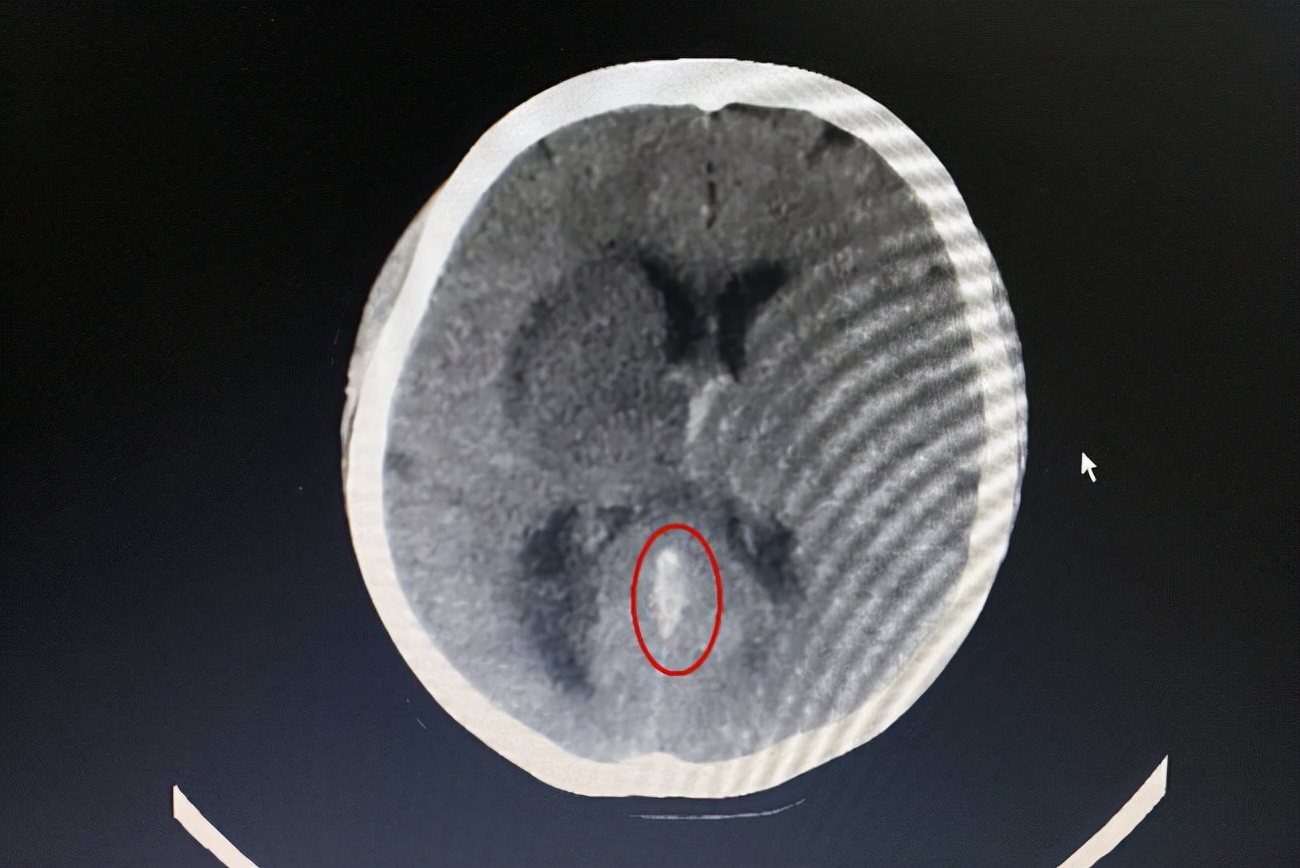

随后家人急忙送往医院进行检查,通过检查发现,王女士已经出现脑积水的迹象,大脑大静脉、大脑内静脉和直窦都有血栓,双侧丘脑、基底节区、胼胝体膝部及透明隔静脉阻塞性脑梗死。

(图源网络)